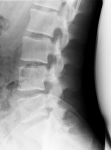

棘突起は折れているか?

病院旅行2006で傷めた腰。日中は忙しくて整形外科で診てもらう時間はありませんでしたが、夕方救外でレントゲンを撮ってもらいました。

腰椎単純(側面)

うん、大丈夫そう。棘突起も折れてないっしょ。

でも相変わらずぷっくら腫れてて触ると痛いの。あと腰曲げたとき。靴下履くの、足の爪切るの、柵を飛び越えるの、、、そういったところに支障が。まぁ「時間薬」ってやつですかね。